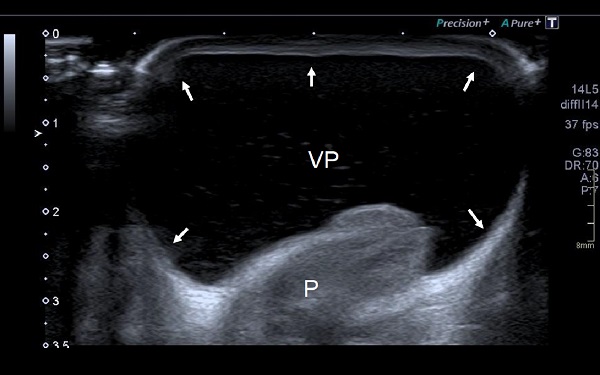

Figura 2. Vejiga prepucial llena de orina, anecoica (VP). Piel del prepucio (flechas). Pene (P)